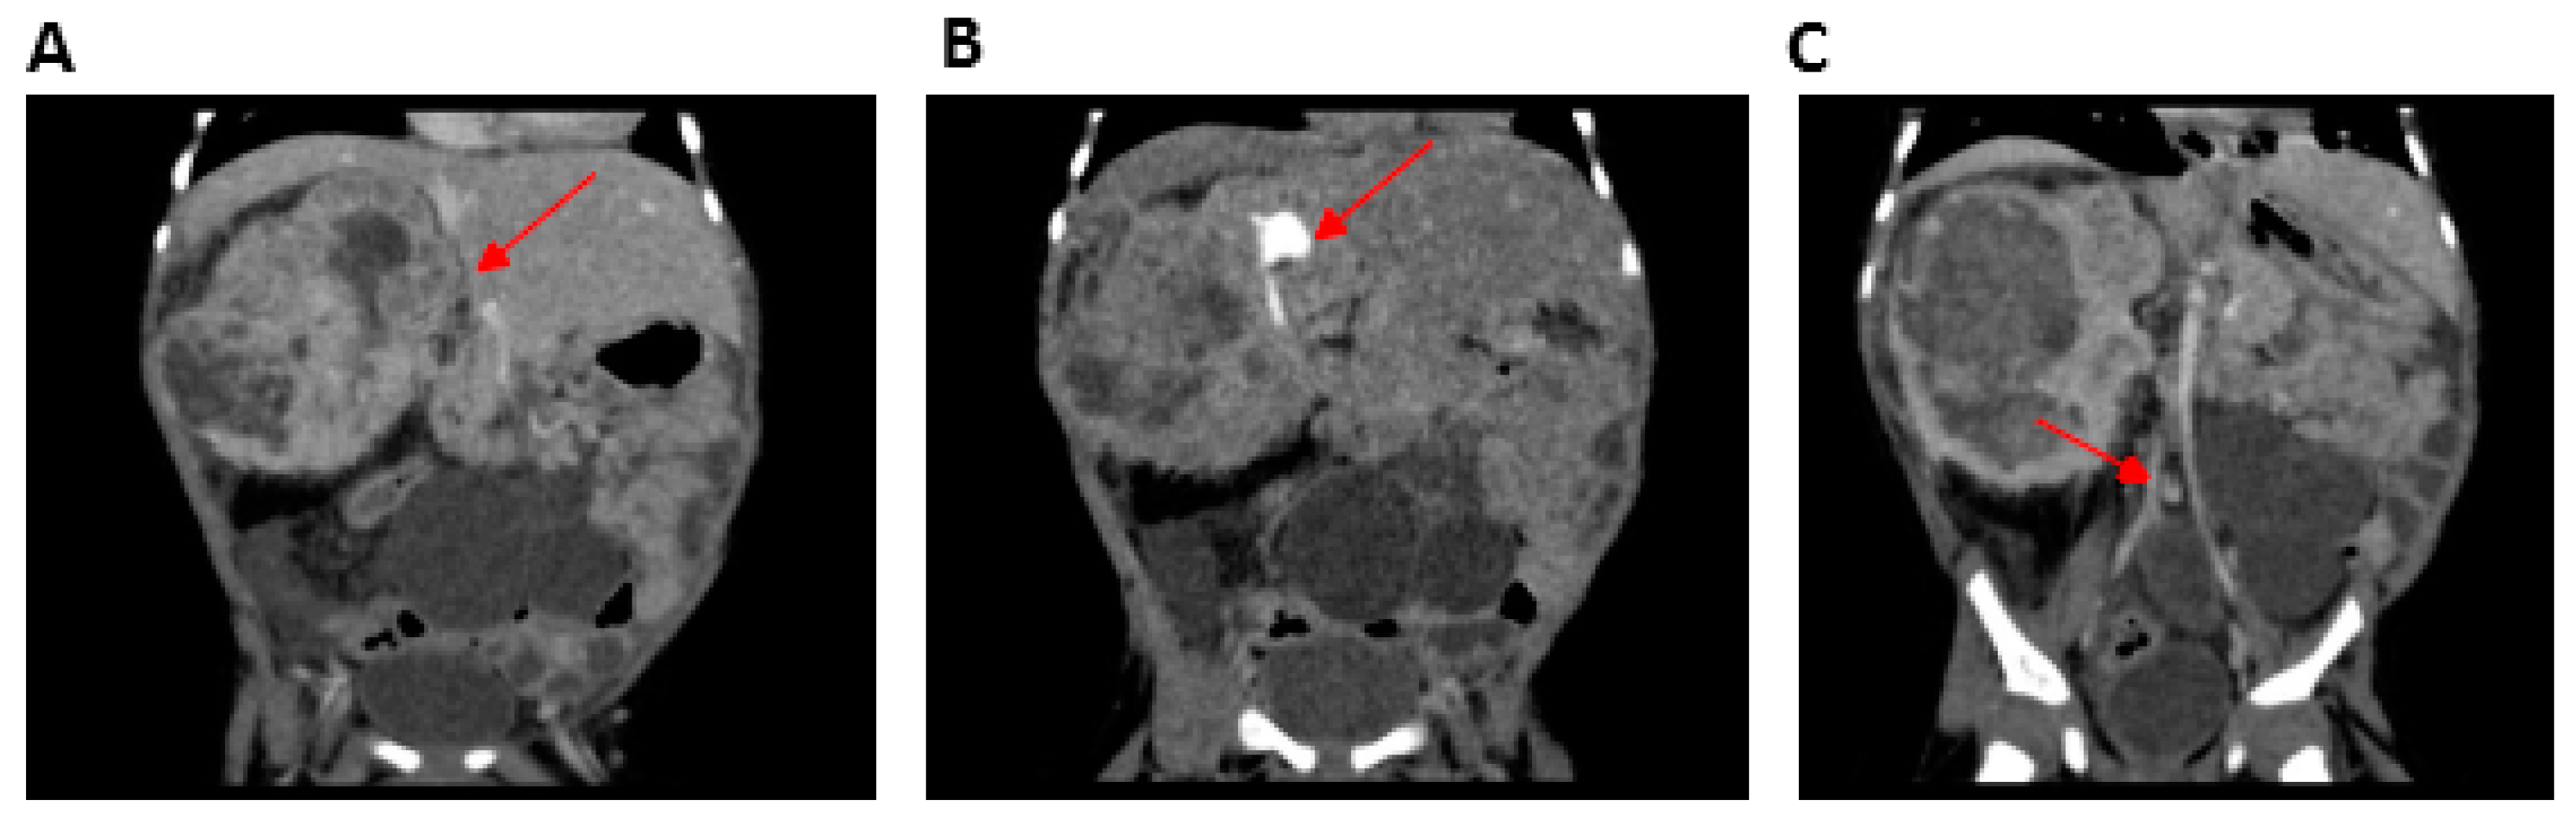

| Multicystic kidney | − | + | NR | NR | NR | |

| Mesoblastic nephroma | − | + | − | NR | NR | |